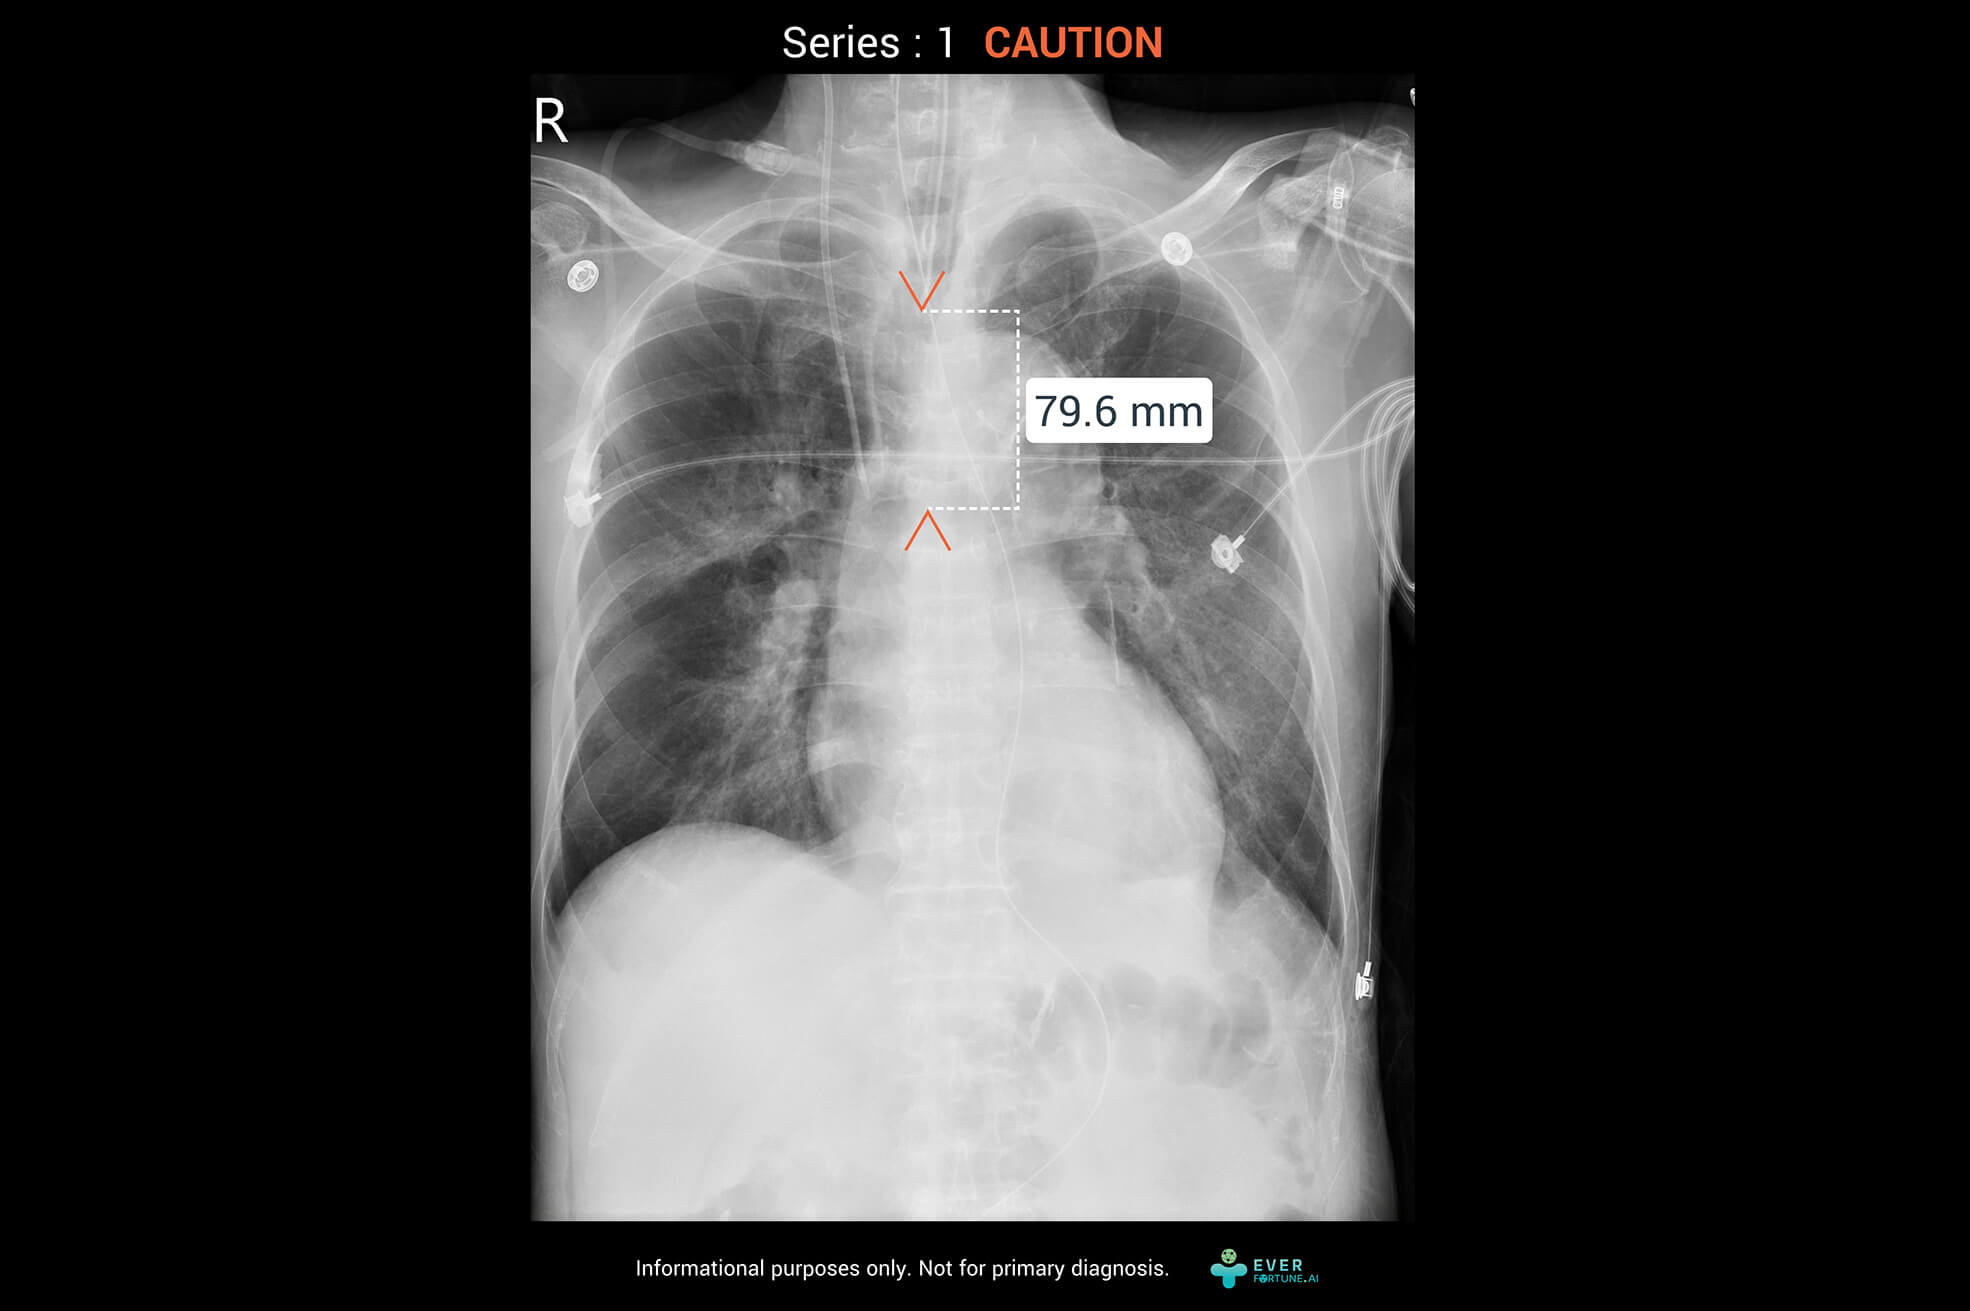

ChestSuite XR Assessment System

Identify 15 abnormal finding in chest X-ray images with heart, lungs and bones. The system as a pre-read assistance enable a quick interpretation and faster decisions